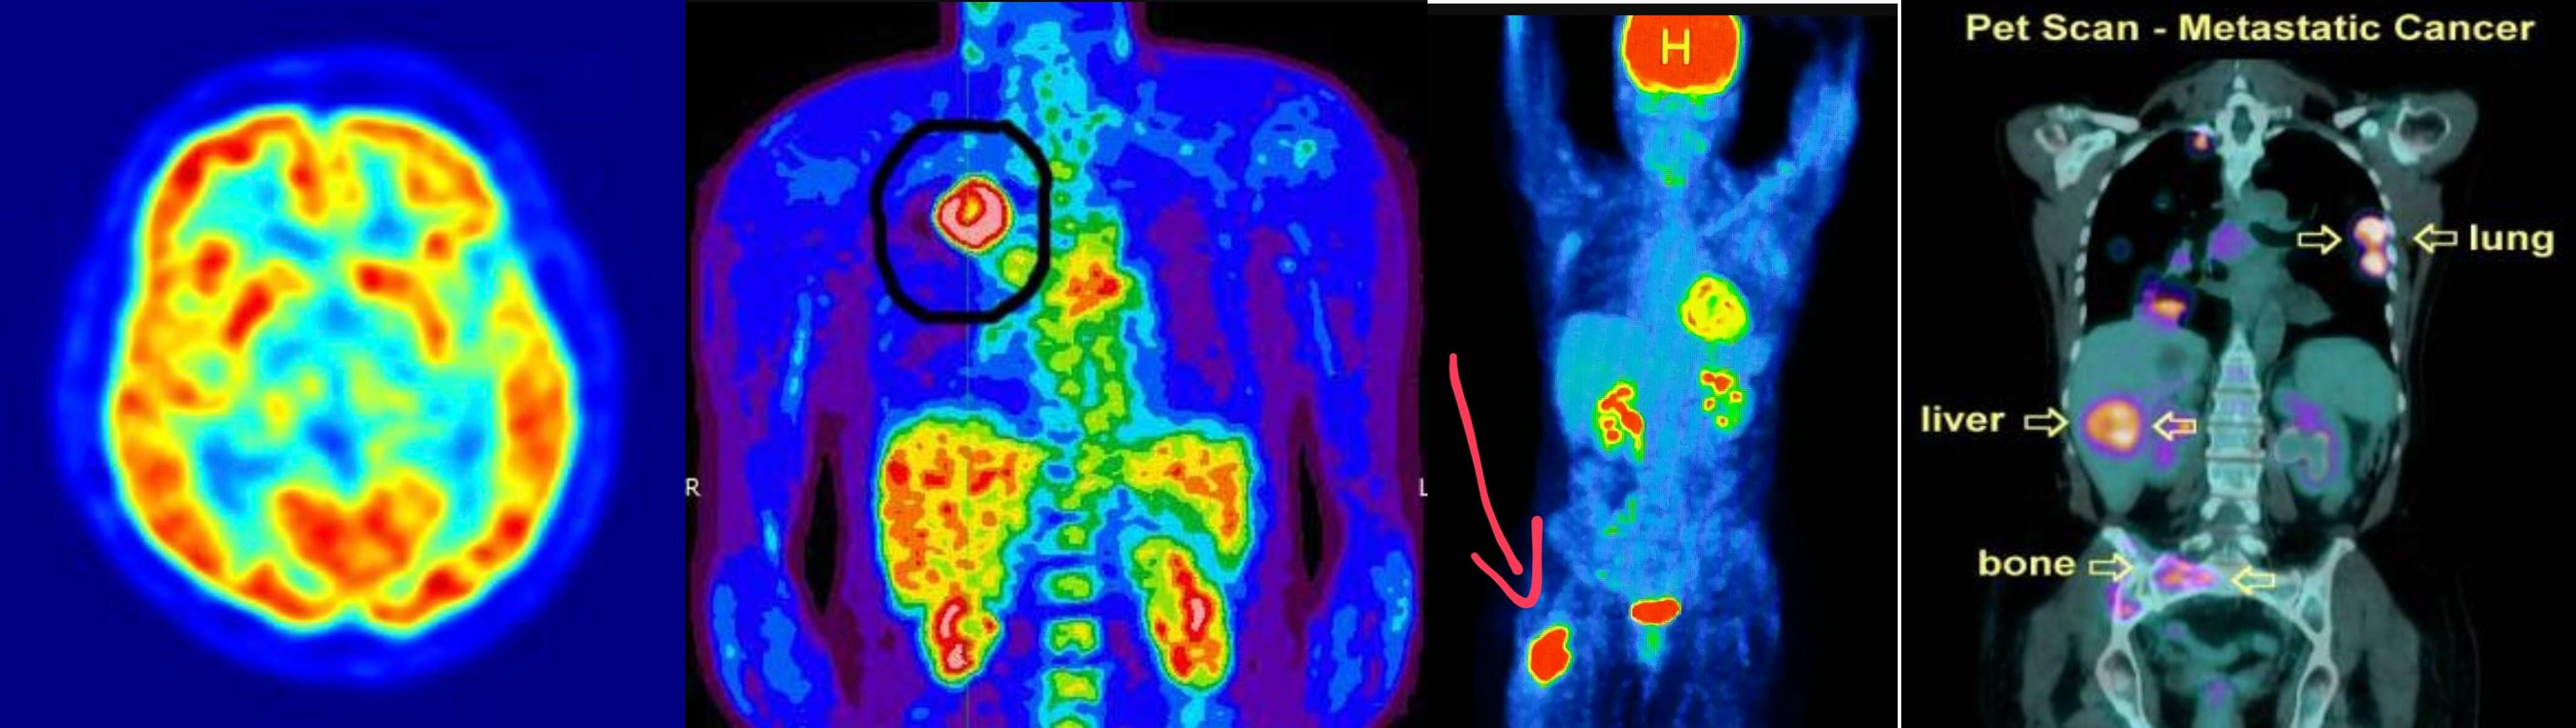

PET SCAN

annual follow up

- soft tissue sarcoma -

- lung cancer metasteseses to bone